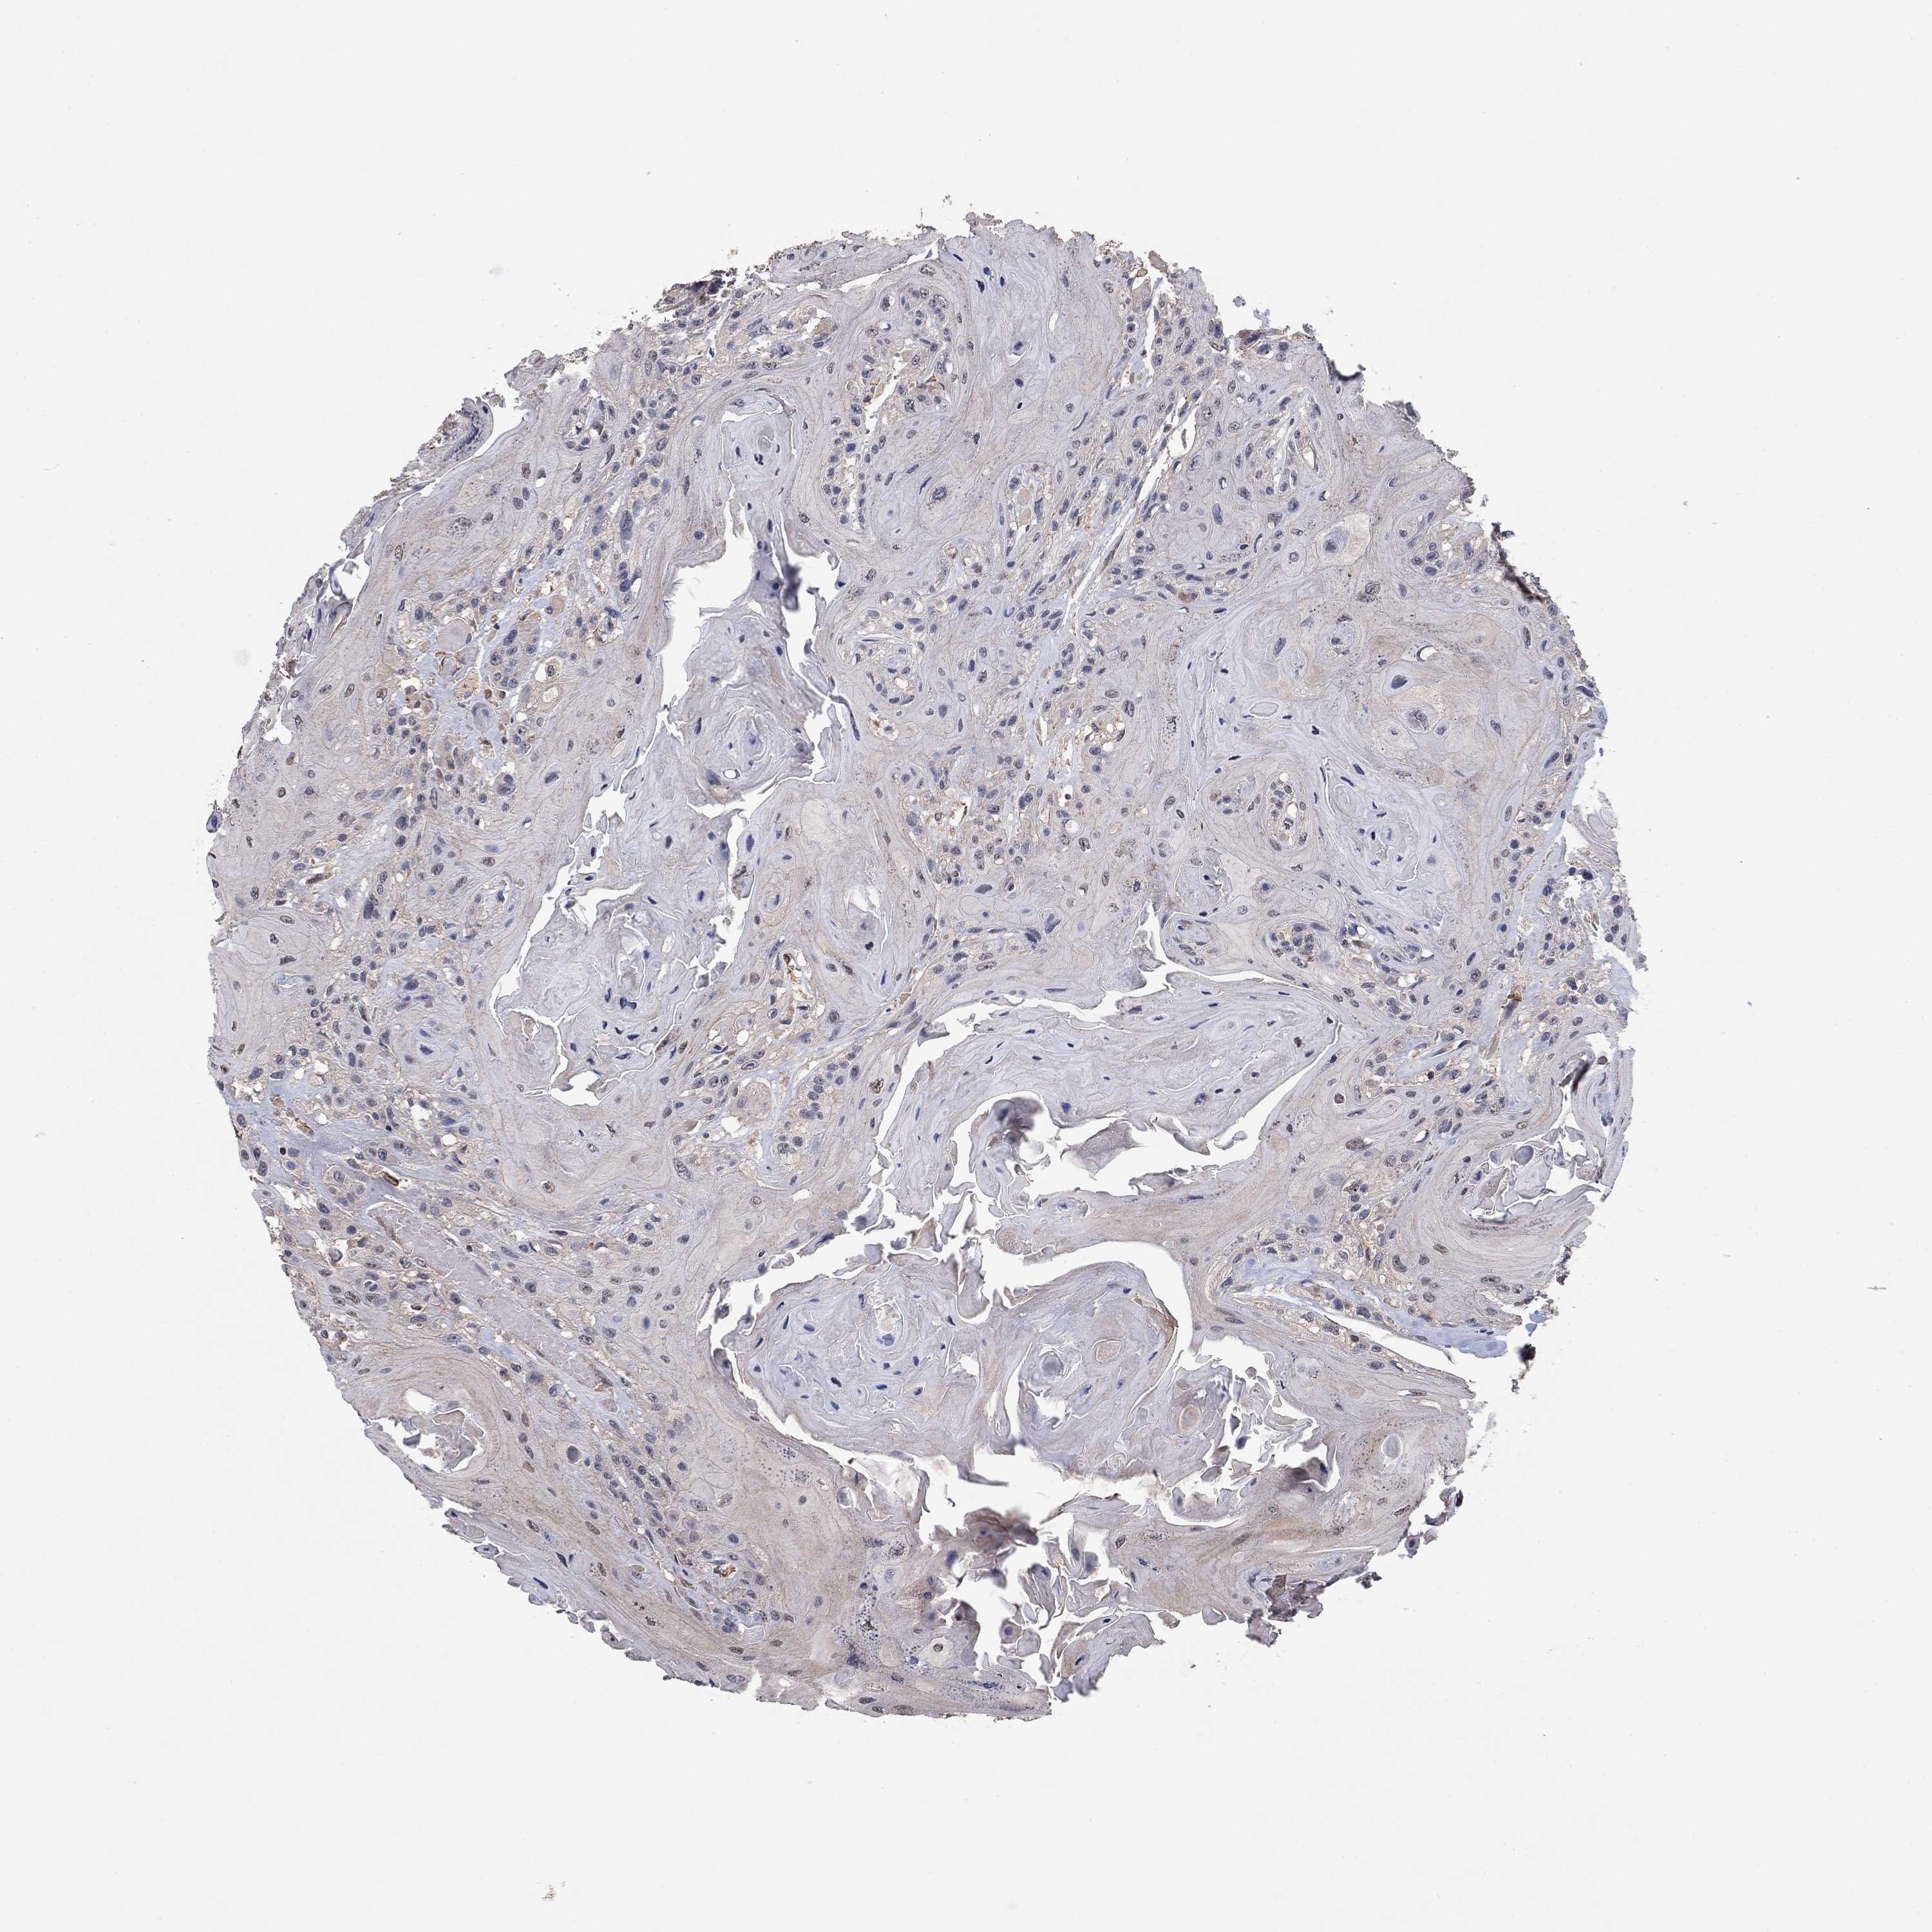

HEAD AND NECK CANCER - Protein expressioni

A mouse-over function shows sample information and annotation data. Click on an image to view it in a full screen mode. Samples can be filtered based on level of antibody staining by selecting one or several of the following categories: high, medium, low and not detected. The assay and annotation is described here.

Antibody stainingi

Antibody staining in the annotated cell types in the current human tissue is reported as not detected, low, medium, or high, based on conventional immunohistochemistry profiling in selected tissues. This score is based on the combination of the staining intensity and fraction of stained cells.

Each image is clickable and will lead to virtual microscopy that enables deeper exploration of all samples and also displays staining intensity scores, fraction scores and subcellular localization as well as patient and tissue information for each sample.

Antibody HPA078654

Staining

High

Medium

Low

Not detected

Intensity

Strong

Moderate

Weak

Negative

Quantity

>75%

75%-25%

<25%

None

Location

Nuclear

Cytoplasmic/membranous

Cytoplasmic/membranous,nuclear

Squamous cell carcinoma, NOS